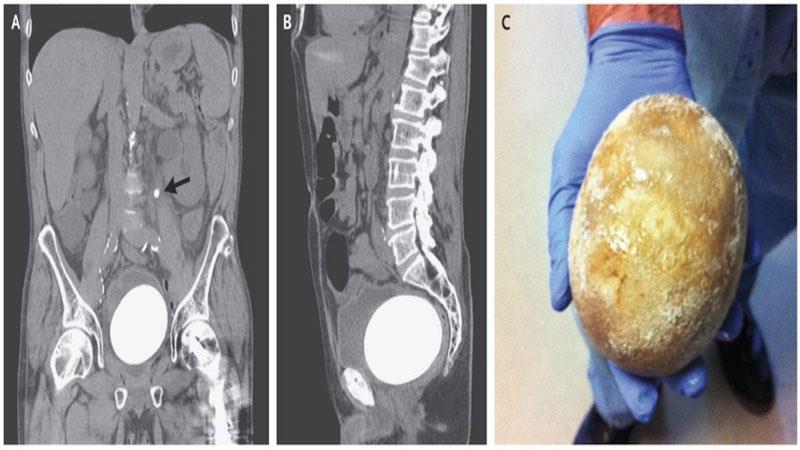

پزیشکەکان لە نەخۆشخانەی "پۆلاکۆڤۆ" سەرکەوتووبوون لە دەرهێنانی بەردێکی یەک کیلۆی لە میزەڵدانی پیاوێکی ڕوسی تەمەن 65 ساڵ.

دکتۆر ئۆلیگ یامیکۆف سەرۆکی بەشی تیمی نەشتەرگەریەکە وتویەتی"بەردێک بەم قەبارەیە زۆر نامۆیە، لە ماوەی 30 ساڵی کارکردن و پسپۆڕیم لەبوارەکەدا ئەمە سێهەم جارە بەردێک بەم قەبارەیە ببینم".

نەخۆشەکە لەدۆخێکی زۆر خراپدا گەیەندراوەتە نەخۆشخانە کە نیشانەی سست بوونی گورچیلە و خوێن بەربوونی میزەڵدانی هەبووە،  پاش ئەوەی ڕەوانەی بەشی نەشتەرگەری کراوە پزیشکەکان زانیویانە ئەو بەردەی دروستبووە بەتەواوەتی ڕێڕەوی میزەڵدانی گرتووە بەڵام تیمەکە نەشتەرگەریەکی سەرکەوتویان بۆ ئەنجامداوە و پزیشکەکان پاش ئەمە نەشتەرگەریەکی دیکەی بۆ ئەنجام دەدەن بۆ ئەوەی توانای میزکردنی ئاسایی ببێتەوە.

پزیشکەکان ئاشکرایان کردووە دروستبوونی بەردێک بەم قەبارەیە هۆکارەکەی پەککەوتنی پرۆستاتە، هەروەها بەو هۆیەوە توانای میزکردنی نەخۆشەکە خراپ بووە و بەردێکی گەورە بەو قەبارەیە لەمیزەڵدانیدا دروستبووە.